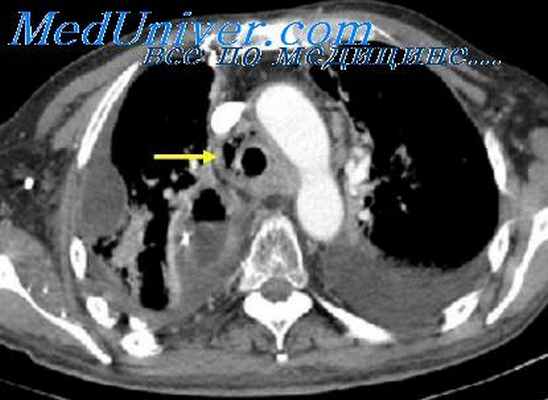

Кроме зобов в верхнем средостении также могут быть обнаружены бронхогенные кисты (более половины всех бронхогенных кист локализуются в верхнем средостении), а также опухоли из нервной ткани (невриномы и нейросаркомы), опухоли плевры (мезотелиома) и опухоли лиматических узлов. Так, плавный переход контура тени пристеночно расположенного образования вблизи тени позвоночника может быть характерен для нейрогенной опухоли. Если тень прилежит к внутренней поверхности грудной стенки, можно заподозрить мезотелиому, опухоль мягких тканей грудной стенки, или (реже) невриному из межреберных нервов. КТ. Выявлено образование верхнего средостения, расположенное частично за рукояткой грудины, прилежащее к стенке трахеи спереди и сбоку, не имеющее признаков инвазивного роста. Видно, что образование не связано с щитовидной железой (располагается отдельно от нее и отделено «полоской» жировой ткани) При компьютерной томографии средостения у пациента выявлено увеличение левой доли щитовидной железы за счет зобной трансформации (увеличенная доля отмечена стрелками на изображениях)

Еще один очень важный признак, который позволяет нам иногда правильно характеризовать характер патологического образования в средостении – это взаимосвязь с другими анатомическими структурами. Классикой жанра здесь является внутригрудной зоб. Он чаще возникает у женщин. Чаще это патология у людей старше 40 – 45 лет. Достаточно частые по статистике образования.

Несмотря на очень большие размеры, оно длительное время может протекать бессимптомно. Важно, что почти всегда мы можем наблюдать связь со щитовидной железой. Это образование располагается в области верхней апертуры. Может быть в переднем или заднем средостении. Как правило, оттесняет и суживает трахею, что на рентгеновских снимках создает очень характерную типичную картину.

Если вы посмотрите на обзорный снимок в прямой проекции, то сразу же будет видно, насколько изменилась конфигурация воздушного столба в трахее на уровне грудино-ключичных расчленений и выше в области верхней апертуры. Трахея оттеснена по дуге вправо и практически достигает контура средостения и несколько сужена.

Почему? Ответ на этот вопрос в компьютерно-томографическом исследовании. Два огромных узла, один из которых располагается на шее. Второй в переднем средостении. Оба гиперваскулярны, неоднородной структуры. Это типичная картина огромных размеров внутригрудного зоба, который занимает переднюю часть средостения.

Это характерная картина, которая должна подлежать интерпретации. Мы опять возвращаемся к опухолям, исходящим из щитовидной железы, которые через верхнюю апертуру спускаются вниз в область грудной полости средостения. Типичные, это хорошо видно, характерные проявления этого патологического образования с оттеснением средостения и локализацией его в области верхней апертуры.

Насколько повышает плотность это патологическое образование. Оно практически соответствует по плотности сосудистым структурам средостения, контрастированию крови в сосудах и камерах сердца. Это характерно для тканей щитовидной железы.

Другой пример. Болезнь Кастельмана. Здесь специально оставлены денситометрические показатели. Средняя плотность образования, которое располагается между типичных образований, между восходящей и нисходящей аортой и оттесняет трахею сзади и справа, составляет почти 140 или 150 единиц (неразборчиво, 15:07).

Практически так же как контрастированная кровь. Очень немногие патологические образования средостения реагируют таким образом на введение контрастного вещества. В этом случае сочетание точной локализации и реакции на контрастный препарат позволяют предположить правильный диагноз.